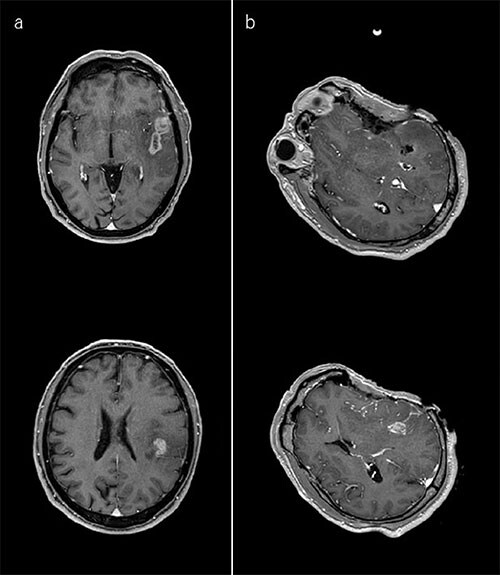

A patient presented with skipped lesions (a). The first intraoperative image confirms resection of the anterior part of the tumor. At that time, the surgeon found it difficult to reach the posterior part because the microscope light did not project the surgical corridor. Accordingly, it was decided to change to another corridor based on the result of the first intraoperative MRI image. The register images for neuronavigation were updated (b). The second intraoperative image shows tumor remnant at the anterior part of thecorridor. The register images for neuronavigation were updated (c). The day after surgery, post-operative images show a satisfactory surgical result (d).